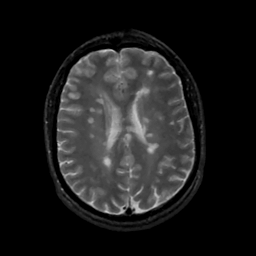

MR Study #14, June 2, 1991 -- Slice #32

[Home][Help][Clinical][Tour 1][Tour 2] Slice 32